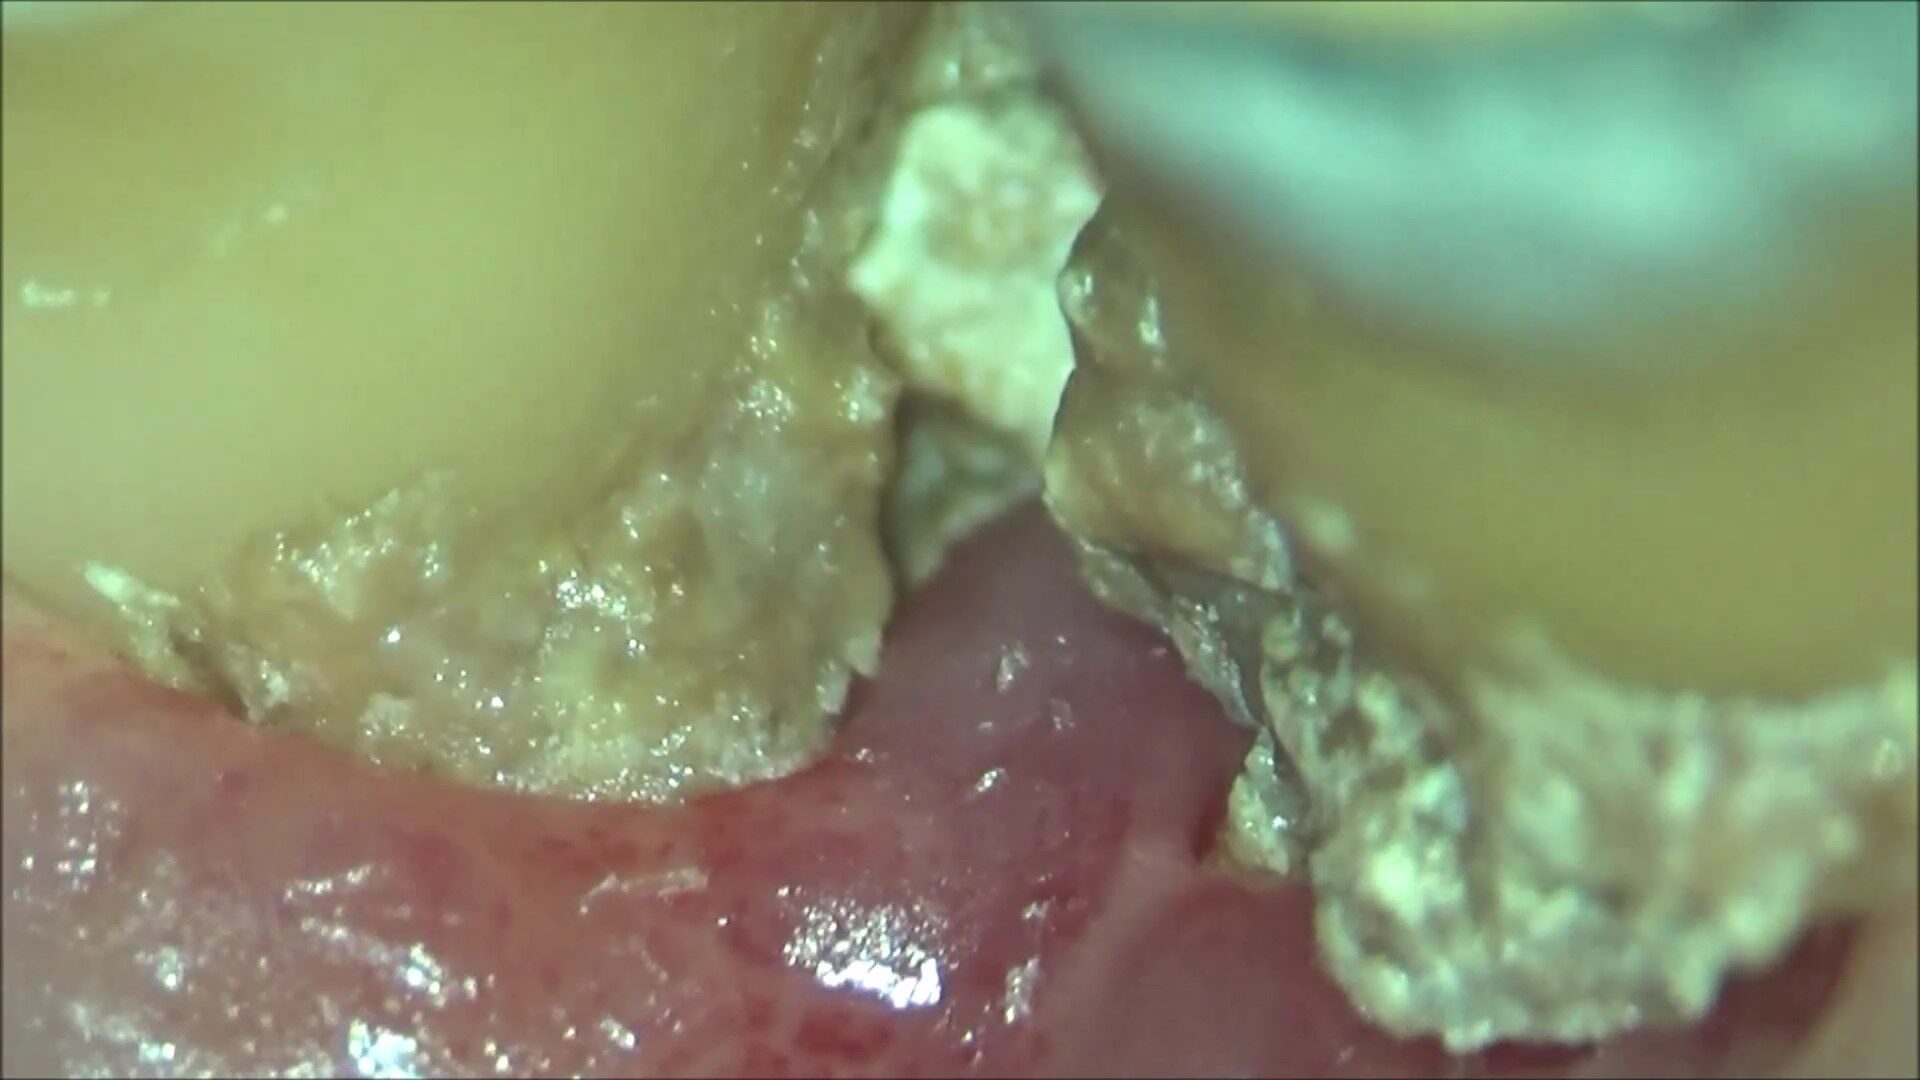

歯周専門治療

こんにちは。南館歯科クリニック、歯科衛生士の佐藤です。 今回は、歯周病治療です。 60代男性。 主訴は、左上の奥歯、歯周病で何度か腫れた。根っこが割れていて、抜かなければならないと言われた。抜かずに済…